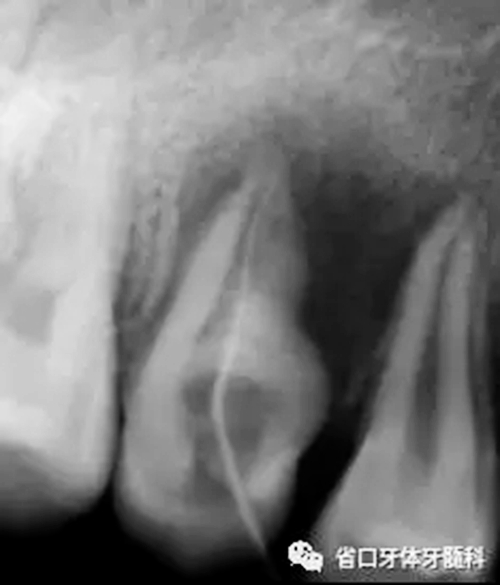

圖2 根尖片(2016-3-19),15未完全萌出,形態(tài)異常, 根尖周和根側(cè)方見低密度影,牙槽骨破壞